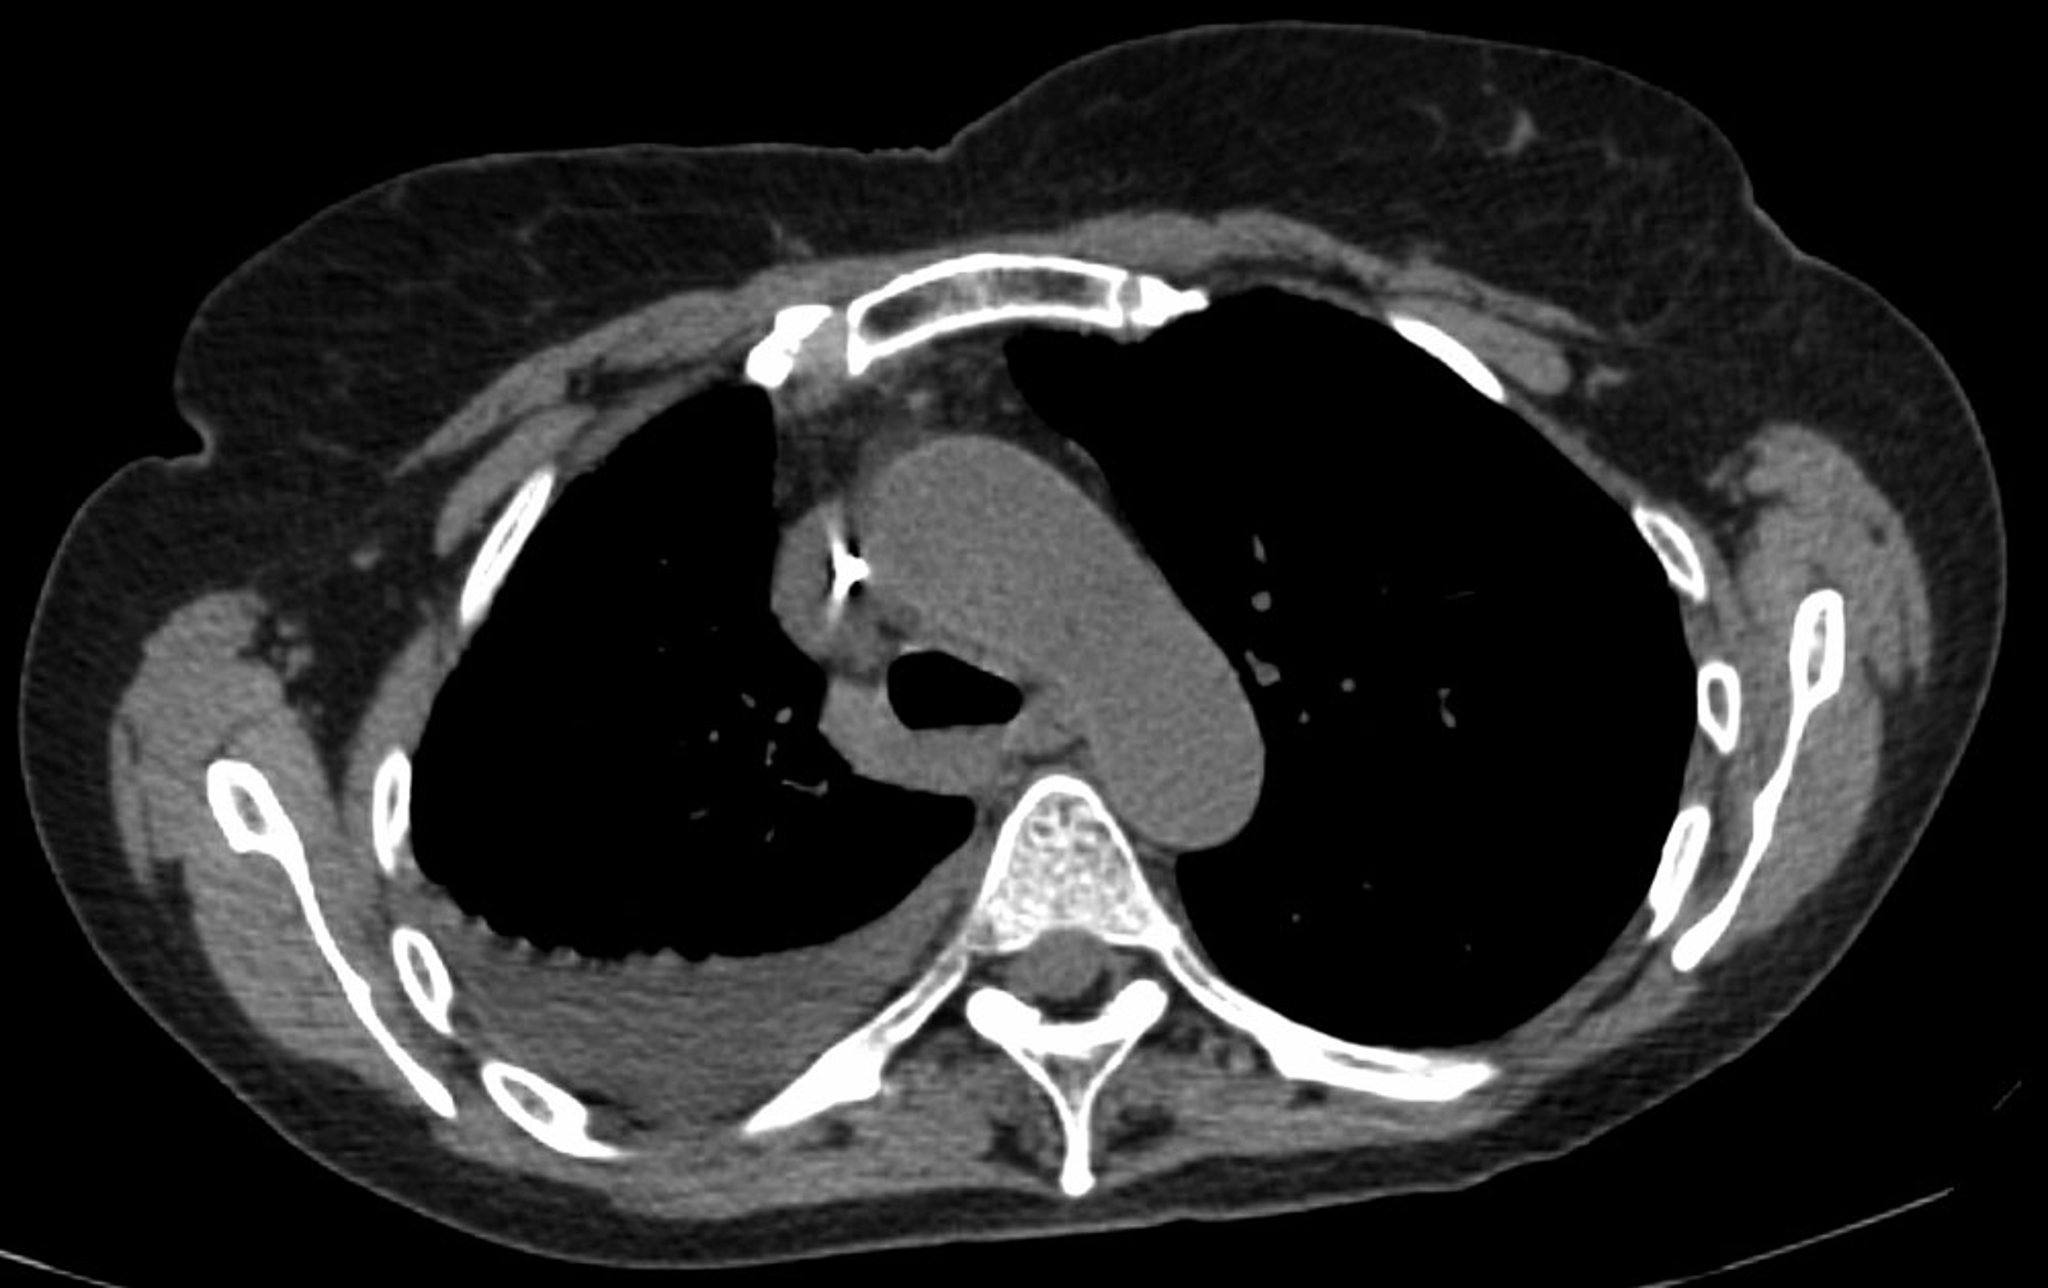

La radiographie de thorax est le premier examen effectué pour confirmer la présence de liquide pleural. La radiographie de thorax en position debout et latérale doit être examinée en cas de suspicion d'épanchement pleural. Dans une radiographie debout, 75 mL de liquide émoussent l'angle costophrénique postérieur. Un émoussement de l'angle latéral costophrénique nécessite habituellement pour apparaître environ 175 mL, mais jusqu'à 500 mL peuvent être nécessaires. Les radiographies en décubitus latéral (avec le côté de l'épanchement vers le bas) peuvent être capables de détecter de petits volumes de liquide plus facilement que les radiographies standard en position debout, en particulier avec un épanchement libre. De plus grands épanchements pleuraux opacifient des parties de l'hémithorax et peuvent provoquer un déplacement médiastinal; les épanchements de > 4 L peuvent entraîner une opacification complète de l'hémithorax et un déplacement controlatéral du médiastin.

Les épanchements cloisonnés sont des collections de liquide piégé par des adhérences pleurales ou dans des scissures pulmonaires. Une imagerie complémentaire (radiographies en décubitus latéral, une TDM du thorax ou une échographie), doit être pratiquée si on ne peut déterminer si une densité radiologique représente du liquide ou des infiltrats parenchymateux, ou si on suspecte que du liquide soit cloisonné ou libre; ces examens sont plus sensibles que les radiographies debout et peuvent détecter de petits volumes de liquide. Les épanchements cloisonnés, en particulier ceux de la scissure horizontale ou oblique, peuvent être confondus avec une masse pulmonaire solide (pseudo-tumeur). Ils peuvent changer de forme et de taille en fonction des changements de position du patient et de la quantité de liquide pleural.

L'échographie thoracique est considérée comme la norme de soins en cas de diagnostic d'un épanchement pleural et est réalisée et interprétée par les médecins au chevet du patient. Elle est très performante pour la détection de petits volumes de liquide pleural et fournit des informations diagnostiques supplémentaires (p. ex., présence d'une septation, d'un épaississement pleural).

La TDM avec contraste veineux est un examen précieux supplémentaire qui fournit des informations sur la prise de contraste pleurale et une éventuelle nodularité pleurale. (La TDM sans contraste peut être utilisée pour l'évaluation initiale mais ne peut pas exclure une malignité ou une infection.) La TDM avec contraste veineux permet d'évaluer le parenchyme pulmonaire sous-jacent à la recherche d'infiltrations ou de masses lorsque le poumon est opacifié par l'épanchement ou lorsque la définition des radiographies de thorax est insuffisante pour distinguer un liquide cloisonné d'une masse solide.